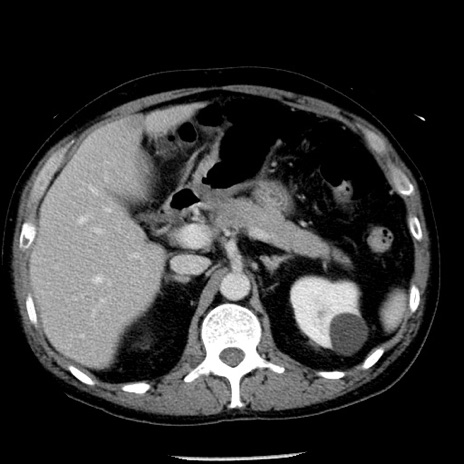

冠状断像

【症例】40歳代男性

【現病歴】2日前から胃痛あり。徐々に周期的な激痛に変化した。本日になっても激痛があるため受診。

【身体所見】意識清明、BT 38-39℃台あり、腹部:膨満、やや硬、右下腹部に圧痛あり。

【データ】WBC 8500、CRP 23.26